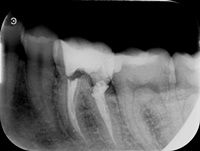

Reendo 46.

Reendo dolnej szóstki.

Wykonany zabieg resekcji wierzcchołka nie pomógł w ustąpieniu obajawów zapalnych. Skuteczne okazało sie dopiero reendo.